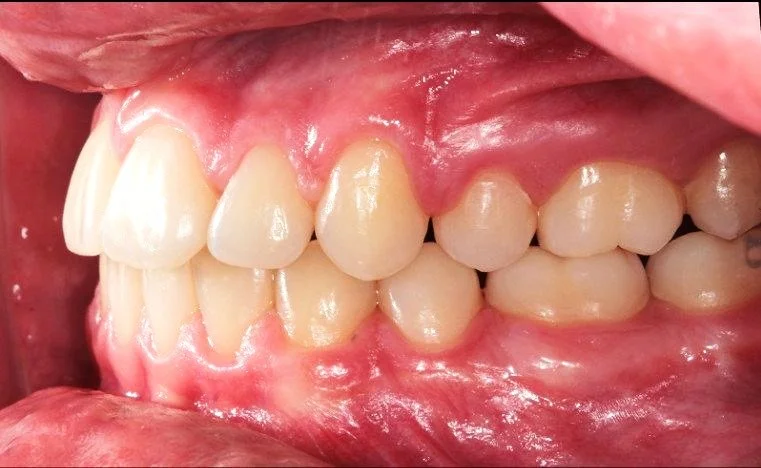

CASO ESTRATTIVO

In alcuni casi, per allineare correttamente i denti senza creare problemi come recessioni gengivali o danni all’osso di supporto, è necessario ricorrere a estrazioni strategiche. Questo accade quando lo spazio in arcata è insufficiente per accogliere tutti i denti in una posizione stabile e armoniosa. Estrarre alcuni elementi dentari permette di ottenere un risultato estetico e funzionale migliore, garantendo una masticazione corretta e preservando la salute dei tessuti gengivali e ossei.

BEFORE

DURING

AFTER

Trattamento con 4 estrazioni di una malocclusione di classe II con proclinazione degli incisivi superiori e inferiori.